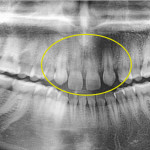

Riassorbimento radicolare esterno in ortodonzia

La pianificazione di un trattamento ortodontico presenta diversi elementi di difficoltà e richiede perciò la piena consapevolezza dei possibili eventi indesiderati che ci si...